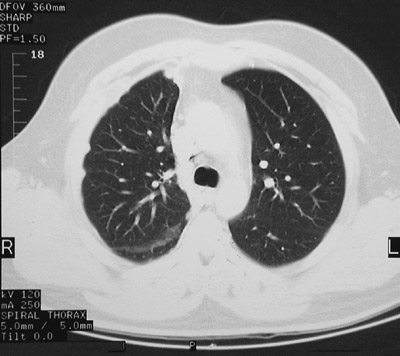

This chest CT scan in "lung window" demonstrates a mesothelioma involving the right pleura with thickening and nodularity. The neoplasm is seen near the base of the lung above and the upper lung below.